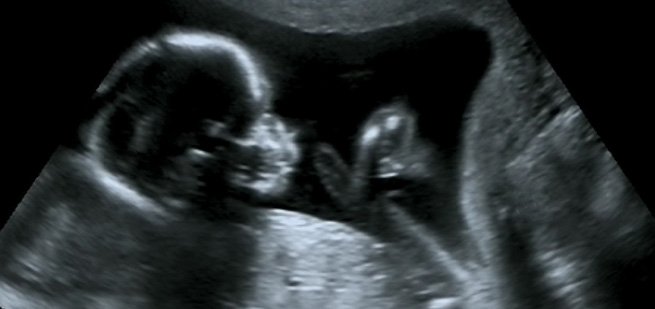

“Your YO home sperm test helped us identify signs of trouble when we were trying to get pregnant. We used YO early on and showed the YO video to our doctor, who helped us develop a new plan. I was the source of our ‘problem’ and YO helped us quickly change some things, with . YO actually saved us time, money and a lot of heartache by helping us understand our fertility challenges. It was a great investment for us and we’re now expecting our baby boy in March. We can’t be more thrilled about our successful journey toward parenthood!”

To say the team was excited is an understatement. We absolutely love that YO was able to help this family identify their fertility issues early. Since then, we’ve been following along with Gabriel and his wife, Nicole.

Baby del Rio should make his appearance toward the end of March, although, according to Gabriel, the doctors are expecting an early delivery.